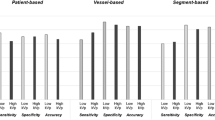

Axial and multiplanar reformatted images were used for analysis. The patient-based image quality of the coronary vessels was subjectively assessed by 2 well-trained, independent, blinded cardiologists who had read the CCTA results of at least 300 patients. The evaluation was patient based after screening the image quality of the 16-segment model of vessel disease proposed by the American Heart Association [16]. All patients were analyzed in a randomized manner, and all segments were evaluated using a 5-point scale: 5, excellent and easily assessable, no artifact in any coronary segment; 4, good, mild artifacts at 1 segment and assessable; 3, evaluable, moderate artifacts on a few segments; 2, evaluable, diagnostic combined with axial images; and 1, not assessable, because of severe artifacts. Reviewers closely reevaluated discordant image quality scores, and if the discordance persisted after a second evaluation, they further evaluated the images individually until they reached a consensus.

Although image noise was higher for 80 kV/350 HU than for 120 kV/350 HU, there was no significant difference in image quality (4.7 ± 0.4 vs. 4.6 ± 0.6, p = 0.390). Neither was there a significant difference in image quality between 80 kV/280 HU and 80 kV/350 HU (4.4 ± 0.7 vs. 4.7 ± 0.4, p = 0.056). Interobserver agreement on image quality was excellent (κ = 0.85).